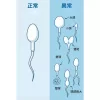

6.遺傳與染色體異常

常見問題:

染色體異常(如Klinefelter癥候群)

Y染色體微缺失

專業建議:

若屬此類原因,需透過基因檢測與醫療介入(如試管嬰兒技術)。

慢性炎癥會導致精子活力下降,並增加畸形率。